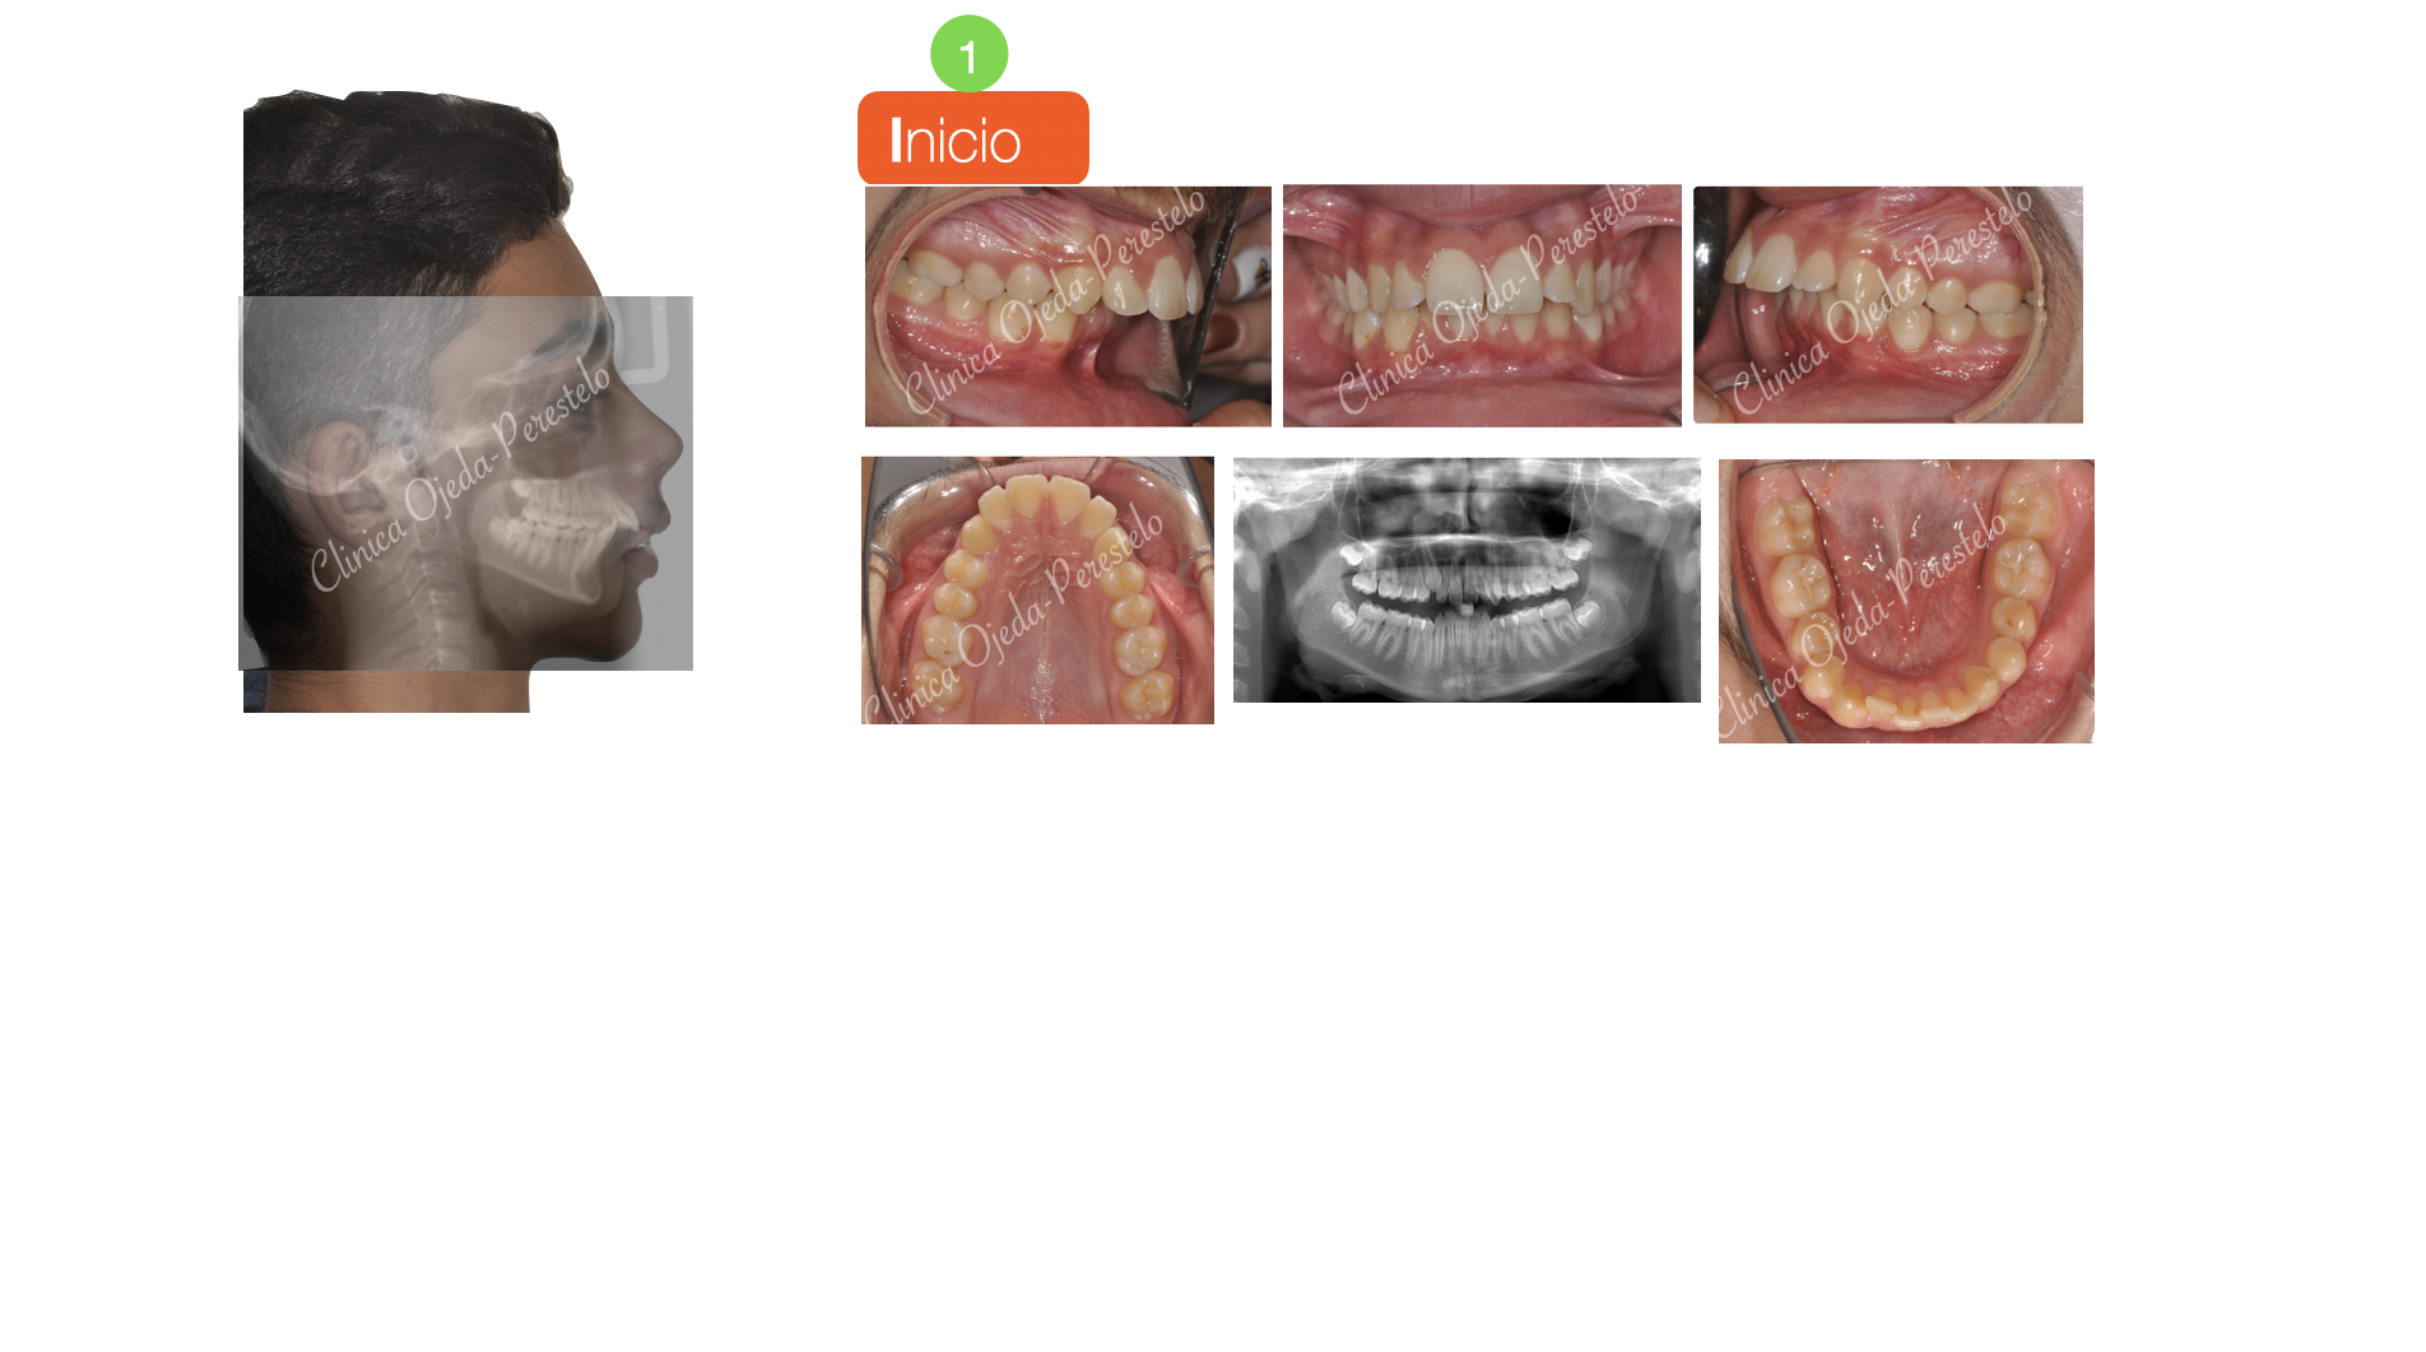

Clase II esquelética en niño con apnea moderada

Paciente niño en dentición definitiva y clase II esquelética de causa Mandibular con apnea obstructiva del sueño. Se decidió tratar con una biela facilitada por Microtornillos a efectos de dotarle de la mayor proyección mandibular posible acompañado de una Ortodoncia. Hoy en día sabemos que avance Mandibular va asociado a un aumento de la Vía Aérea,mejorando su grado de permeabilización.